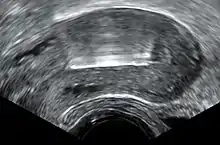

Transvaginal ultrasonography showing a perforated copper IUD as a hyperechoic (rendered as bright) line at right, 3 centimeters away from the uterus at left. The IUD is surrounded by a hypoechoic (dark) foreign-body granuloma.

Transvaginal ultrasonography visualizing an IUD with copper in the optimal location within the uterus.